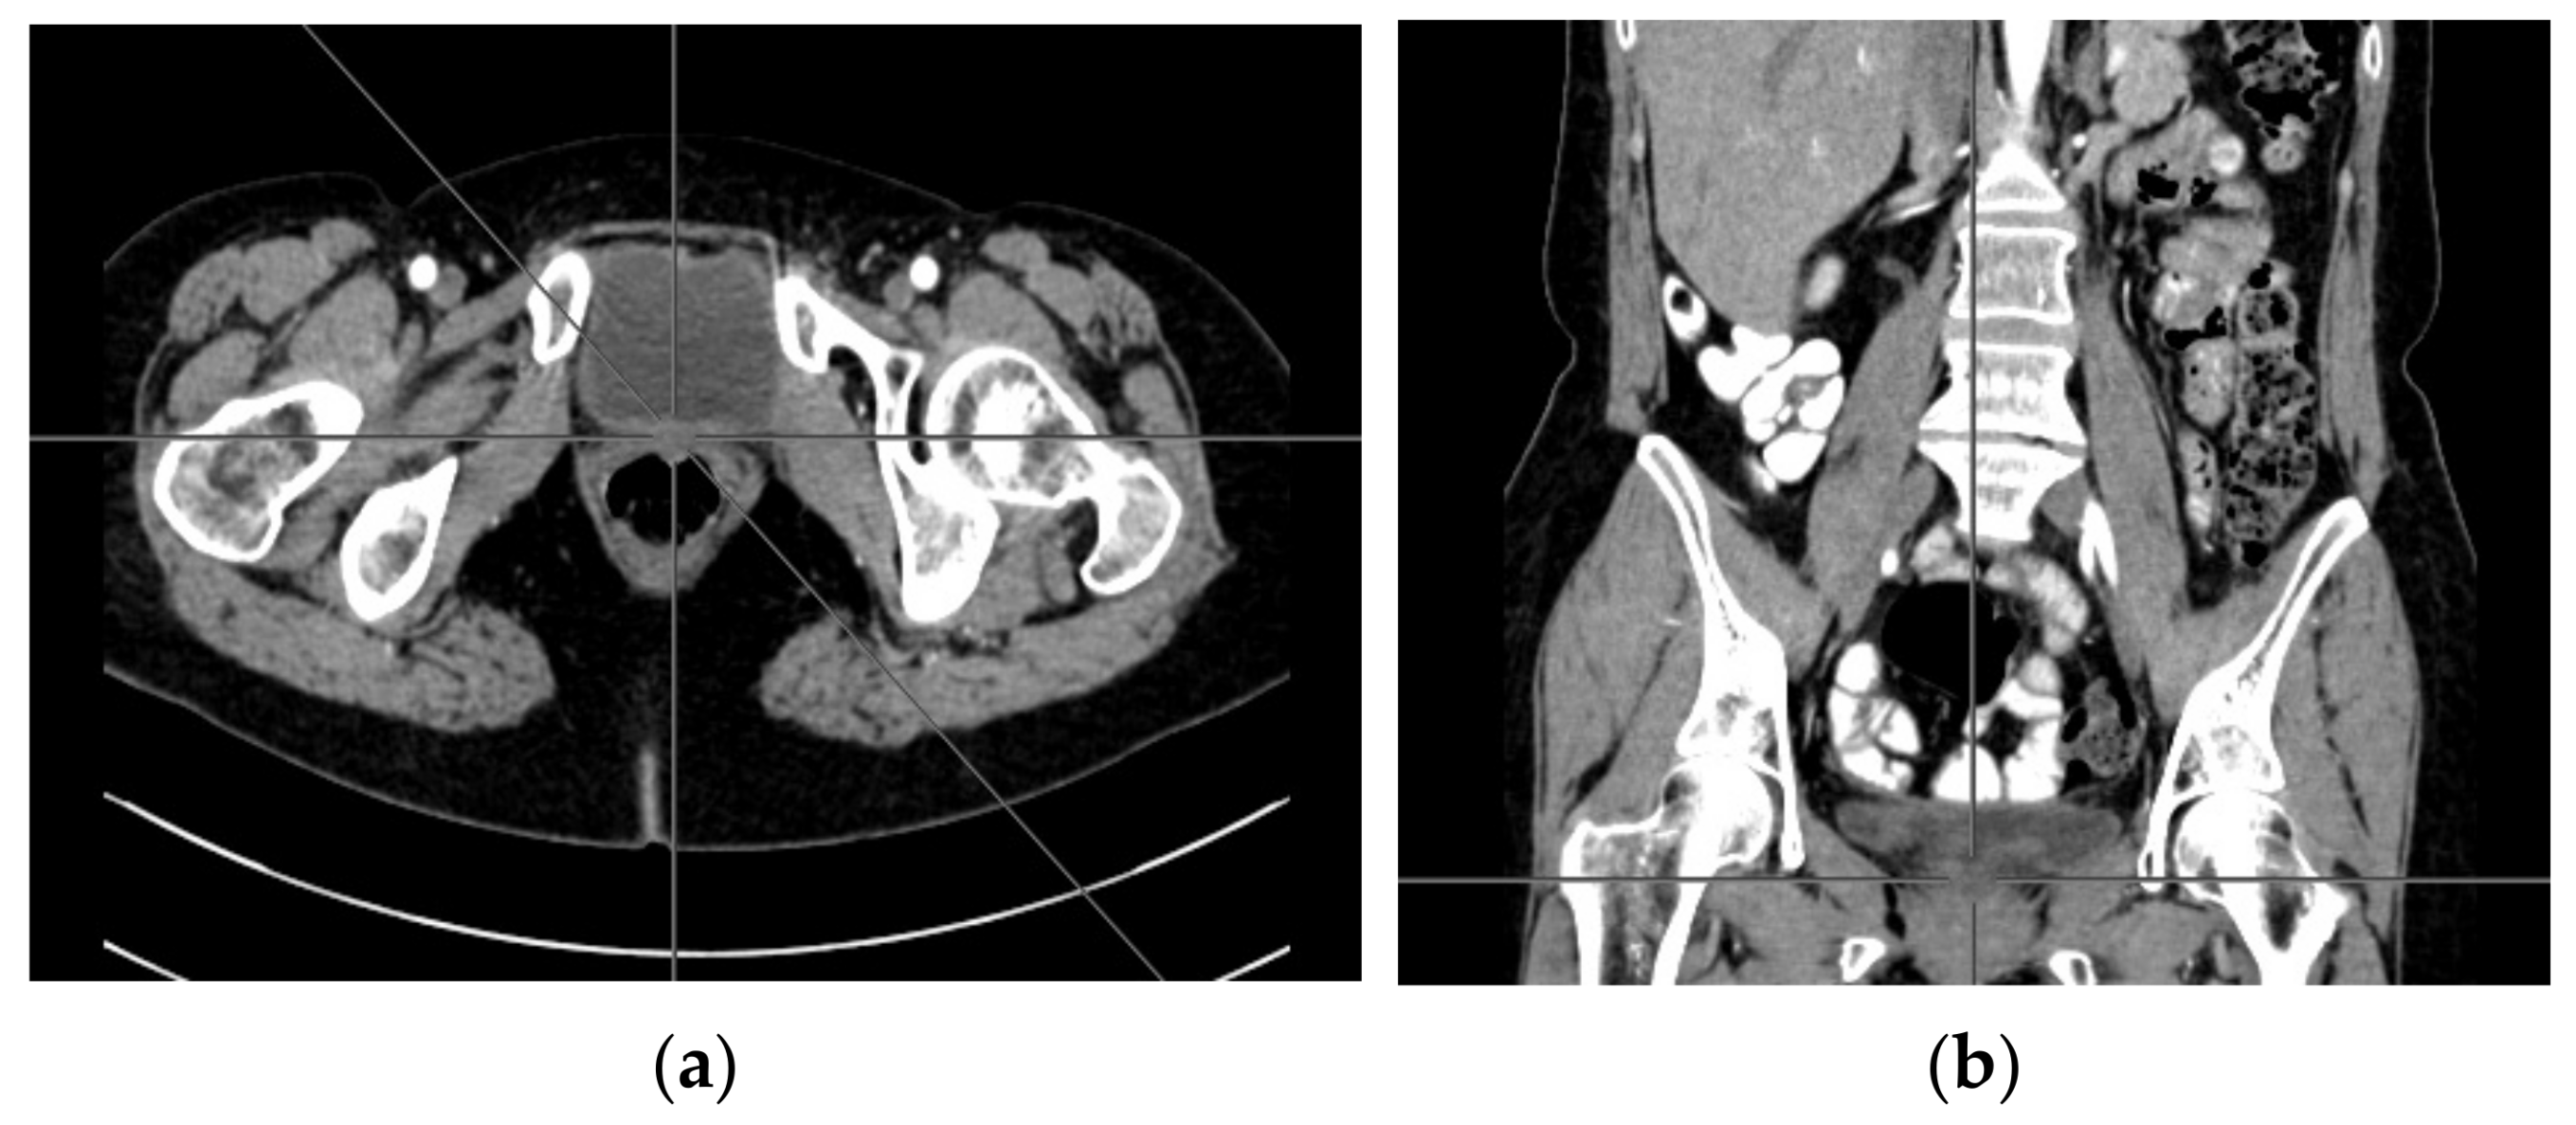

A computer tomography of the abdomen and pelvis was also performed every 3 months for the possible detection of ovarian cancer recurrence. No CT changes suggestive of recurrence were observed in the patient during the treatment. There are illustrates scans on the same section from CT performed at the beginning of PARP inhibitor treatment (Figure 2) and before 48 cycle of olaparib chemotherapy (Figure 3).

Figure 3.

(a–d) CT scans performed before 48 cycle of olaparib treatment.